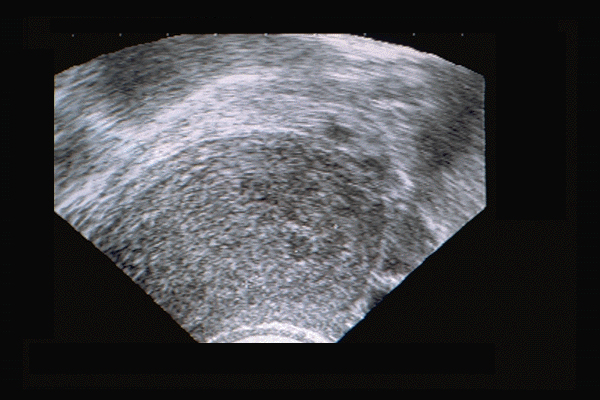

Adénomyose utérine. Myomètre hyperéchogène hétérogène avec cavités fundiques à contenu finement échogène - aspect vermoulu. Adénomyose "cavitaire". Révélée par algoménorrhée.